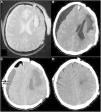

Hinged craniotomy is an alternative surgical technique that can be used in place of decompressive craniectomy to treat refractory intracranial hypertension. This procedure has the advantage of avoiding the need for a second surgery to replace the bone, while giving a good control of intracranial pressure. However, there is no consistent literature about complications of hinged craniotomy. In particular, there are no reported cases of contralateral subdural effusion after hinged craniotomy. In this article we present a case of a 55-years-old man who developed contralateral subdural effusion after a hinged craniotomy for intracranial hypertension, and how we handled it. Therefore, we explored literature to better understand the pathogenesis of contralateral subdural effusion, treatments and possible prevention strategies.